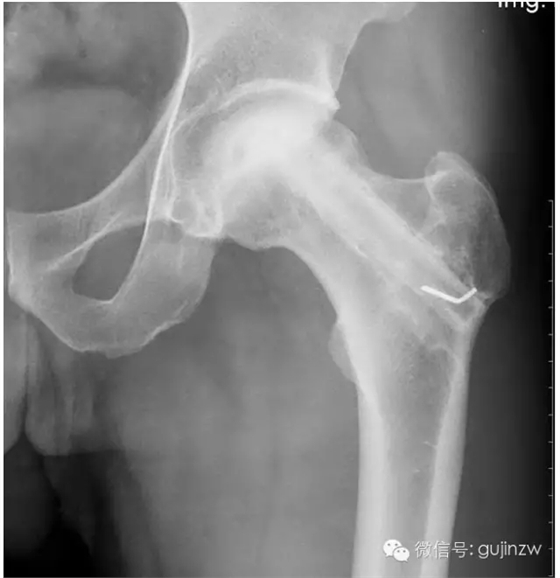

4、骨阻擋:髖關節(jié)脫位髖臼加蓋